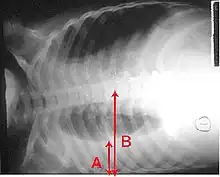

A pleural effusion appears as an area of whiteness on a standard posteroanterior chest X-ray.[14] Normally, the space between the visceral pleura and the parietal pleura cannot be seen. A pleural effusion infiltrates the space between these layers. Because the pleural effusion has a density similar to water, it can be seen on radiographs. Since the effusion has greater density than the rest of the lung, it gravitates towards the lower portions of the pleural cavity. The pleural effusion behaves according to basic fluid dynamics, conforming to the shape of pleural space, which is determined by the lung and chest wall. If the pleural space contains both air and fluid, then an air-fluid level that is horizontal will be present, instead of conforming to the lung space.[15] Chest radiographs in the lateral decubitus position (with the patient lying on the side of the pleural effusion) are more sensitive and can detect as little as 50 mL of fluid. Between 250 and 600mL of fluid must be present before upright chest X-rays can detect a pleural effusion (e.g., blunted costophrenic angles).[16]

A pleural effusion as seen on lateral upright chest x-ray- Pleural effusion as seen behind the heart.[19]